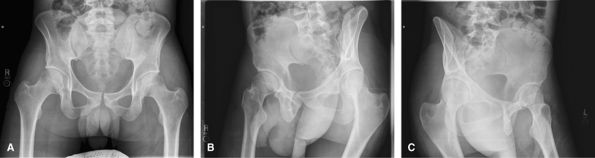

Sacroiliac Joints

Good initial screening test for sacroiliitis. MRI is more sensitive and saves radiation to the gonads.

![]() |

Figure 40 (A) AP pelvis. (B) AP oblique of right sacroiliac joint. (C) AP oblique of left sacroiliac joint.

Acetabulum (Judet Views)

Good for assessing acetabular fractures, but now usually

replaced by oblique images of whole pelvis. Requires 4 images: 2 RPO and

2 LPO images, collimated to affected side only.

Figure 41 (A) AP pelvis. (B) Right posterior oblique (RPO) CR on up-side. (C) Right posterior oblique (RPO) CR on down-side. (D) Left posterior oblique (LPO) CR on up-side. (E) Left posterior oblique (LPO) CR on down-side.

Oblique Pelvis

Also good for assessing fractures about the acetabular.

CT is good for the initial assessment, but when there is a need to

follow up fractures, oblique views are usually used.

Figure 42 (A) AP pelvis. (B) Right posterior oblique (RPO). (C) Left posterior oblique (LPO).

Inlet/Outlet

Good to assess for pelvic fractures involving the pubic

rami and sacrum. CT is good for the initial assessment, but when there

is a need to follow up fractures at these locations, inlet and outlet

views are usually used.

Figure 43 (A) AP pelvis. (B) AP axial outlet view. (C) AP axial inlet view.